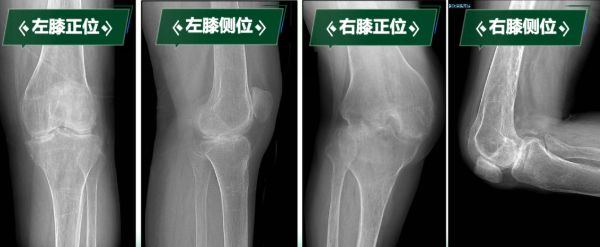

“真不敢相信,我能站起來,還能走路……”劉阿姨因罹患類風濕性關節炎多年,骨質受到嚴重侵蝕,導致雙膝關節逐漸纖維性強直,更加棘手的是,雙膝強直于兩個極端體位,左膝關節無法